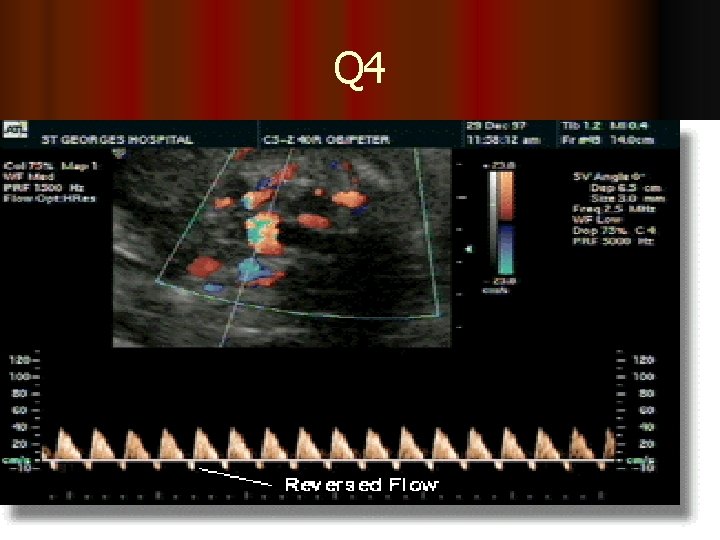

Q 4

The resistance index (RI) is the most commonly used index to measure the uterine artery flow as it is unlikely to have absent or reverse end Diastolic (EDF) flow. Although the pulsatility index (PI) can also be used 3. High resistance waveforms in the uterine artery with early diastolic notching in the second trimester are asssociated with the later development of preeclampsia, IUGR, placental abruption and intrauterine death. 4. notches of the uterine artery waveform with a high RI, hold the most risk of complicated pregnancies, although it is still to be established wether the notch or the high RI is the best indicator of poor outcome 5. Systole (Sys) and diastole (D) are identified in green Note that diastole is less at 20 weeks (yellow ellipse) than at 36 weeks (red ellipse). 6. This illustrates absent diastolic flow during diastole. When this occurs there is abnormal resistance in the placenta which results in a marked decrease in blood flow from the fetus to the placenta.